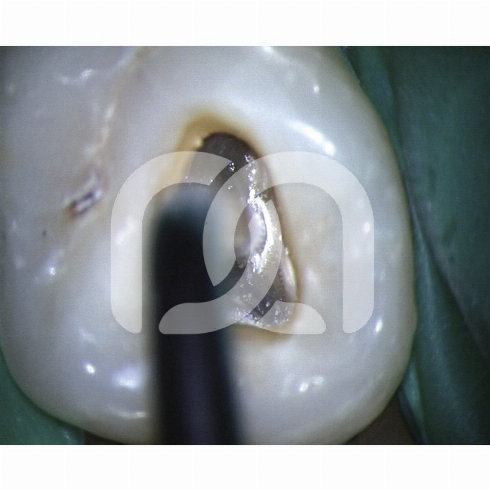

Insertsà ultrasons pour la finition de la cavité d'accès et la localisation des entrées canalaires.- Un insert endodontique Une indication clinique.- Start-X N° 1 : Finition des parois de la cavité d'accès.- Start-X N° 2 : Localisation du canal du 2ème canal racine mésio-vestibulaire.- Start-XN° 3 : Recherche et ouverture des canaux calcifiés.- Start-X N° 4 : Retrait des tenons métalliques.- Start-X N° 5 : Mise en forme de l'anatomie du plancher pulpaire. Caractéristiques - Partie active micro-fraisée : efficacité de coupe associée à une finition parfaite.- Port dirrigation : refroidit linsert et évite l'échauffement de la dent traitée, en particulier pour le descellement de tenon nécessitant une puissance élevée. Avantages - Une grande précision de travail.- Un gain de temps.- Excellente résistance à la fracture.